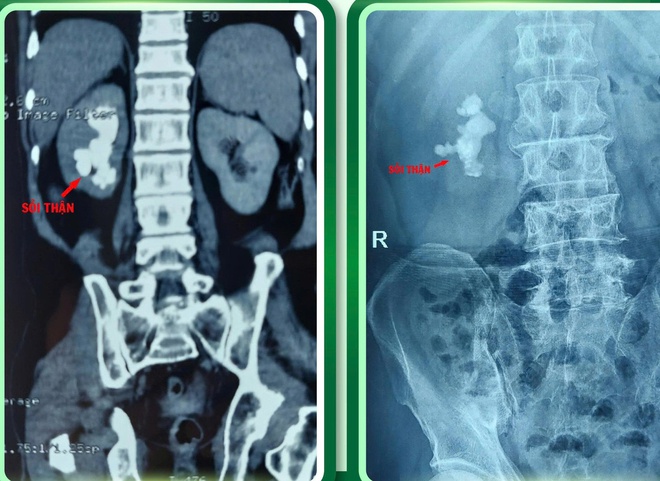

Bệnh nhân là ông Nguyễn Bá H. (51 tuổi, trú xã Quỳ Hợp, Nghệ An), nhập viện trong tình trạng thể trạng suy kiệt, mắc sỏi san hô thận phải kích thước lớn kèm xơ gan. Đây là nhóm bệnh nhân có nguy cơ chảy máu rất cao, mọi can thiệp phẫu thuật đều tiềm ẩn rủi ro đe dọa tính mạng.

Sau hội chẩn toàn diện, ê-kíp Khoa Ngoại tổng hợp đã thống nhất lựa chọn phẫu thuật nội soi lấy sỏi thận qua da (Mini PCNL) – phương pháp ít xâm lấn, giảm tổn thương nhu mô thận và hạn chế tối đa nguy cơ chảy máu.